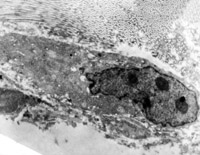

5-2-2 伤后第1天,,,,毛细血管内皮细胞核固缩,,,,管腔内血液凝集和瘀滞  TEM×6000